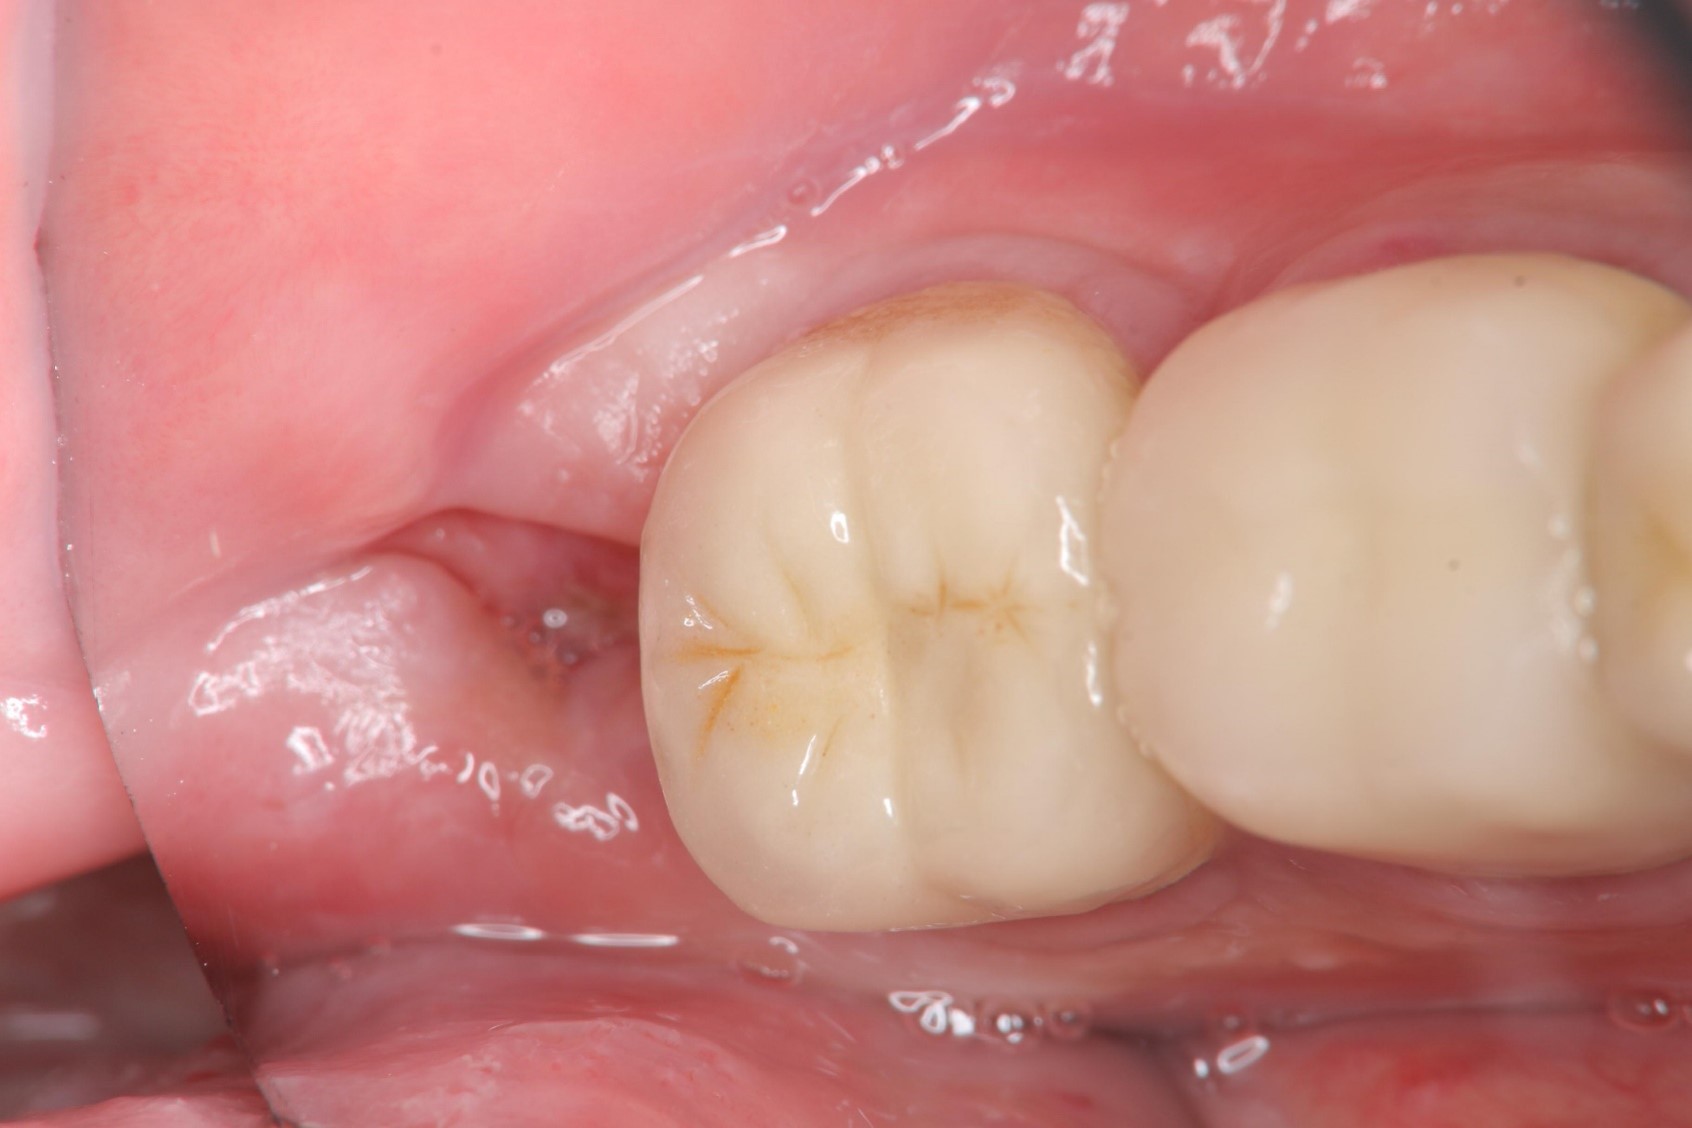

1週後傷口癒合良好

術前、術後比較